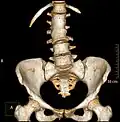

Congenital block vertebra in the lumbar spine (partial vertebrae 3 and 4). The rear portion of the disc still exists. -